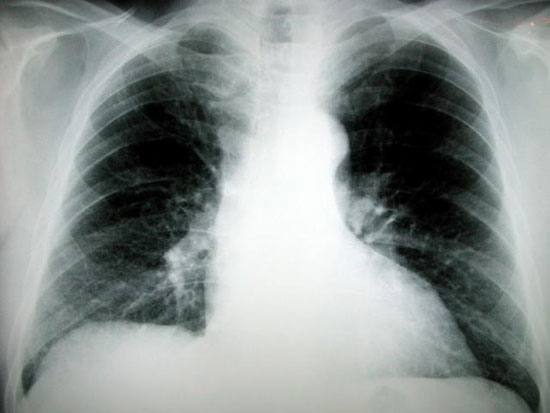

Cuba sắp ra mắt vắcxin có thể điều trị ung thư phổi

Trang medicalxpress ngày 8/9 đưa tin các bệnh nhân bị ung thư phổi giai đoạn cuối sắp được trang bị một công cụ điều trị nữa khi nhà chức trách y tế Cuba thông báo sắp tung ra vắcxin điều trị ung thư phổi đầu tiên trên thế giới. Loại vắcxin mang tên CimaVax EGF được dành cho những bệnh nhân bị ung thư phổi giai đoạn thứ ba và thứ tư nhưng không có tiến triển với các biện pháp điều trị khác như hóa trị và xạ trị.

"Loại vắcxin này có thể biến ung thư thành một căn bệnh mãn tính có thể khống chế được, bằng cách tạo ra các kháng thể chống lại các protein gây ra sự phát triển tế bào không kiểm soát được. Tuy không phải là chặn đứng căn bệnh này, nhưng vắcxin này giúp cải thiện rõ rệt sức khỏe của những bệnh nhân đang ốm nặng," bà Gisela Gonzalez thuộc Trung tâm Miễn dịch học Phân tử (CIM) ở Havana, trưởng nhóm nghiên cứu của dự án nói.

Nhóm nghiên cứu trên đã thực hiện nghiên cứu lâm sàng và thử nghiệm trên hơn 1.000 bệnh nhân ung thư phổi ở Cuba, nơi loại vắcxin này được phát miễn phí. Do Cuba có nhiều người hút thuốc lá nên ung thư phổi là nguyên nhân gây tử vong hàng đầu ở 12 trong tổng số 15 tỉnh ở nước này. Vắcxin ngừa ung thư phổi nói trên là kết quả của quá trình nghiên cứu 25 năm của các nhà khoa học CIM đối với những căn bệnh liên quan đến hút thuốc lá.

Trong tương lai, các nhà nghiên cứu có kế hoạch áp dụng những nguyên lý tương tự của vắcxin CimaVAX-EGF để điều trị các khối u ung thư khác, như ung thư tuyến tiền liệt, tử cung, và ung thư vú. Theo Tổ chức Y tế Thế giới, ung thư phổi là loại ung thư phổ biến và nguy hiểm nhất, khiến 1,4 triệu người trên thế giới tử vong mỗi năm. Mặc dù những phương pháp điều trị hiện tại có thể nâng cao tỷ lệ sống cho bệnh nhân ung thư khi được phát hiện sớm, nhưng đối với những bệnh nhân bị ung thư phổi giai đoạn cuối thì tỷ lệ sống được 5 năm chỉ chưa đầy 1%.